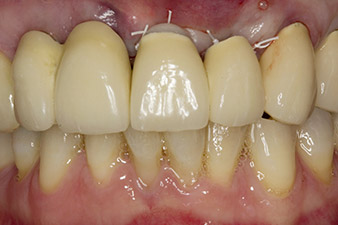

pilot drilling is performed with the new Implantmed and the WS-56 L contra-angle handpiece

Fig. 2: Two months later the pilot drilling is performed with the new Implantmed and the WS-56 L contra-angle handpiece (programme P1, ratio 1:1). The cooling is performed via the spray tube positioned on the left (for right-handed users).

Following primary healing, the soft tissues were shaped using the basally lined bridge. Two months later the site was exposed by a slightly palatal alveolar ridge incision (Fig 2). The dimensions of the alveolar bone proved to be sufficient at position 22. Figures 2 and 4 show the preparation of the implant bed, the tapping and the implantation using Implantmed.